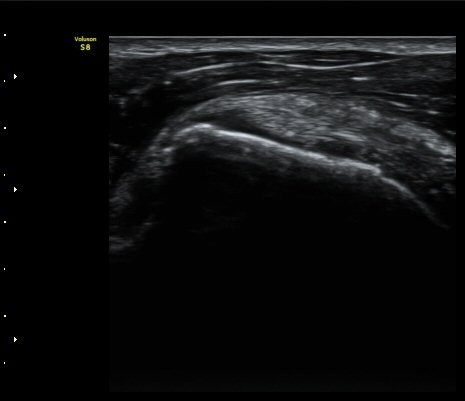

°ß°©ÇÏ±Ù°Ç Á¾´Ü¸é°Ë»ç¿¡¼­ ƯÀÌ ¼Ò°ßÀ» º¸ÀÌÁö ¾ÊÀ½(»çÁø 2, 3)